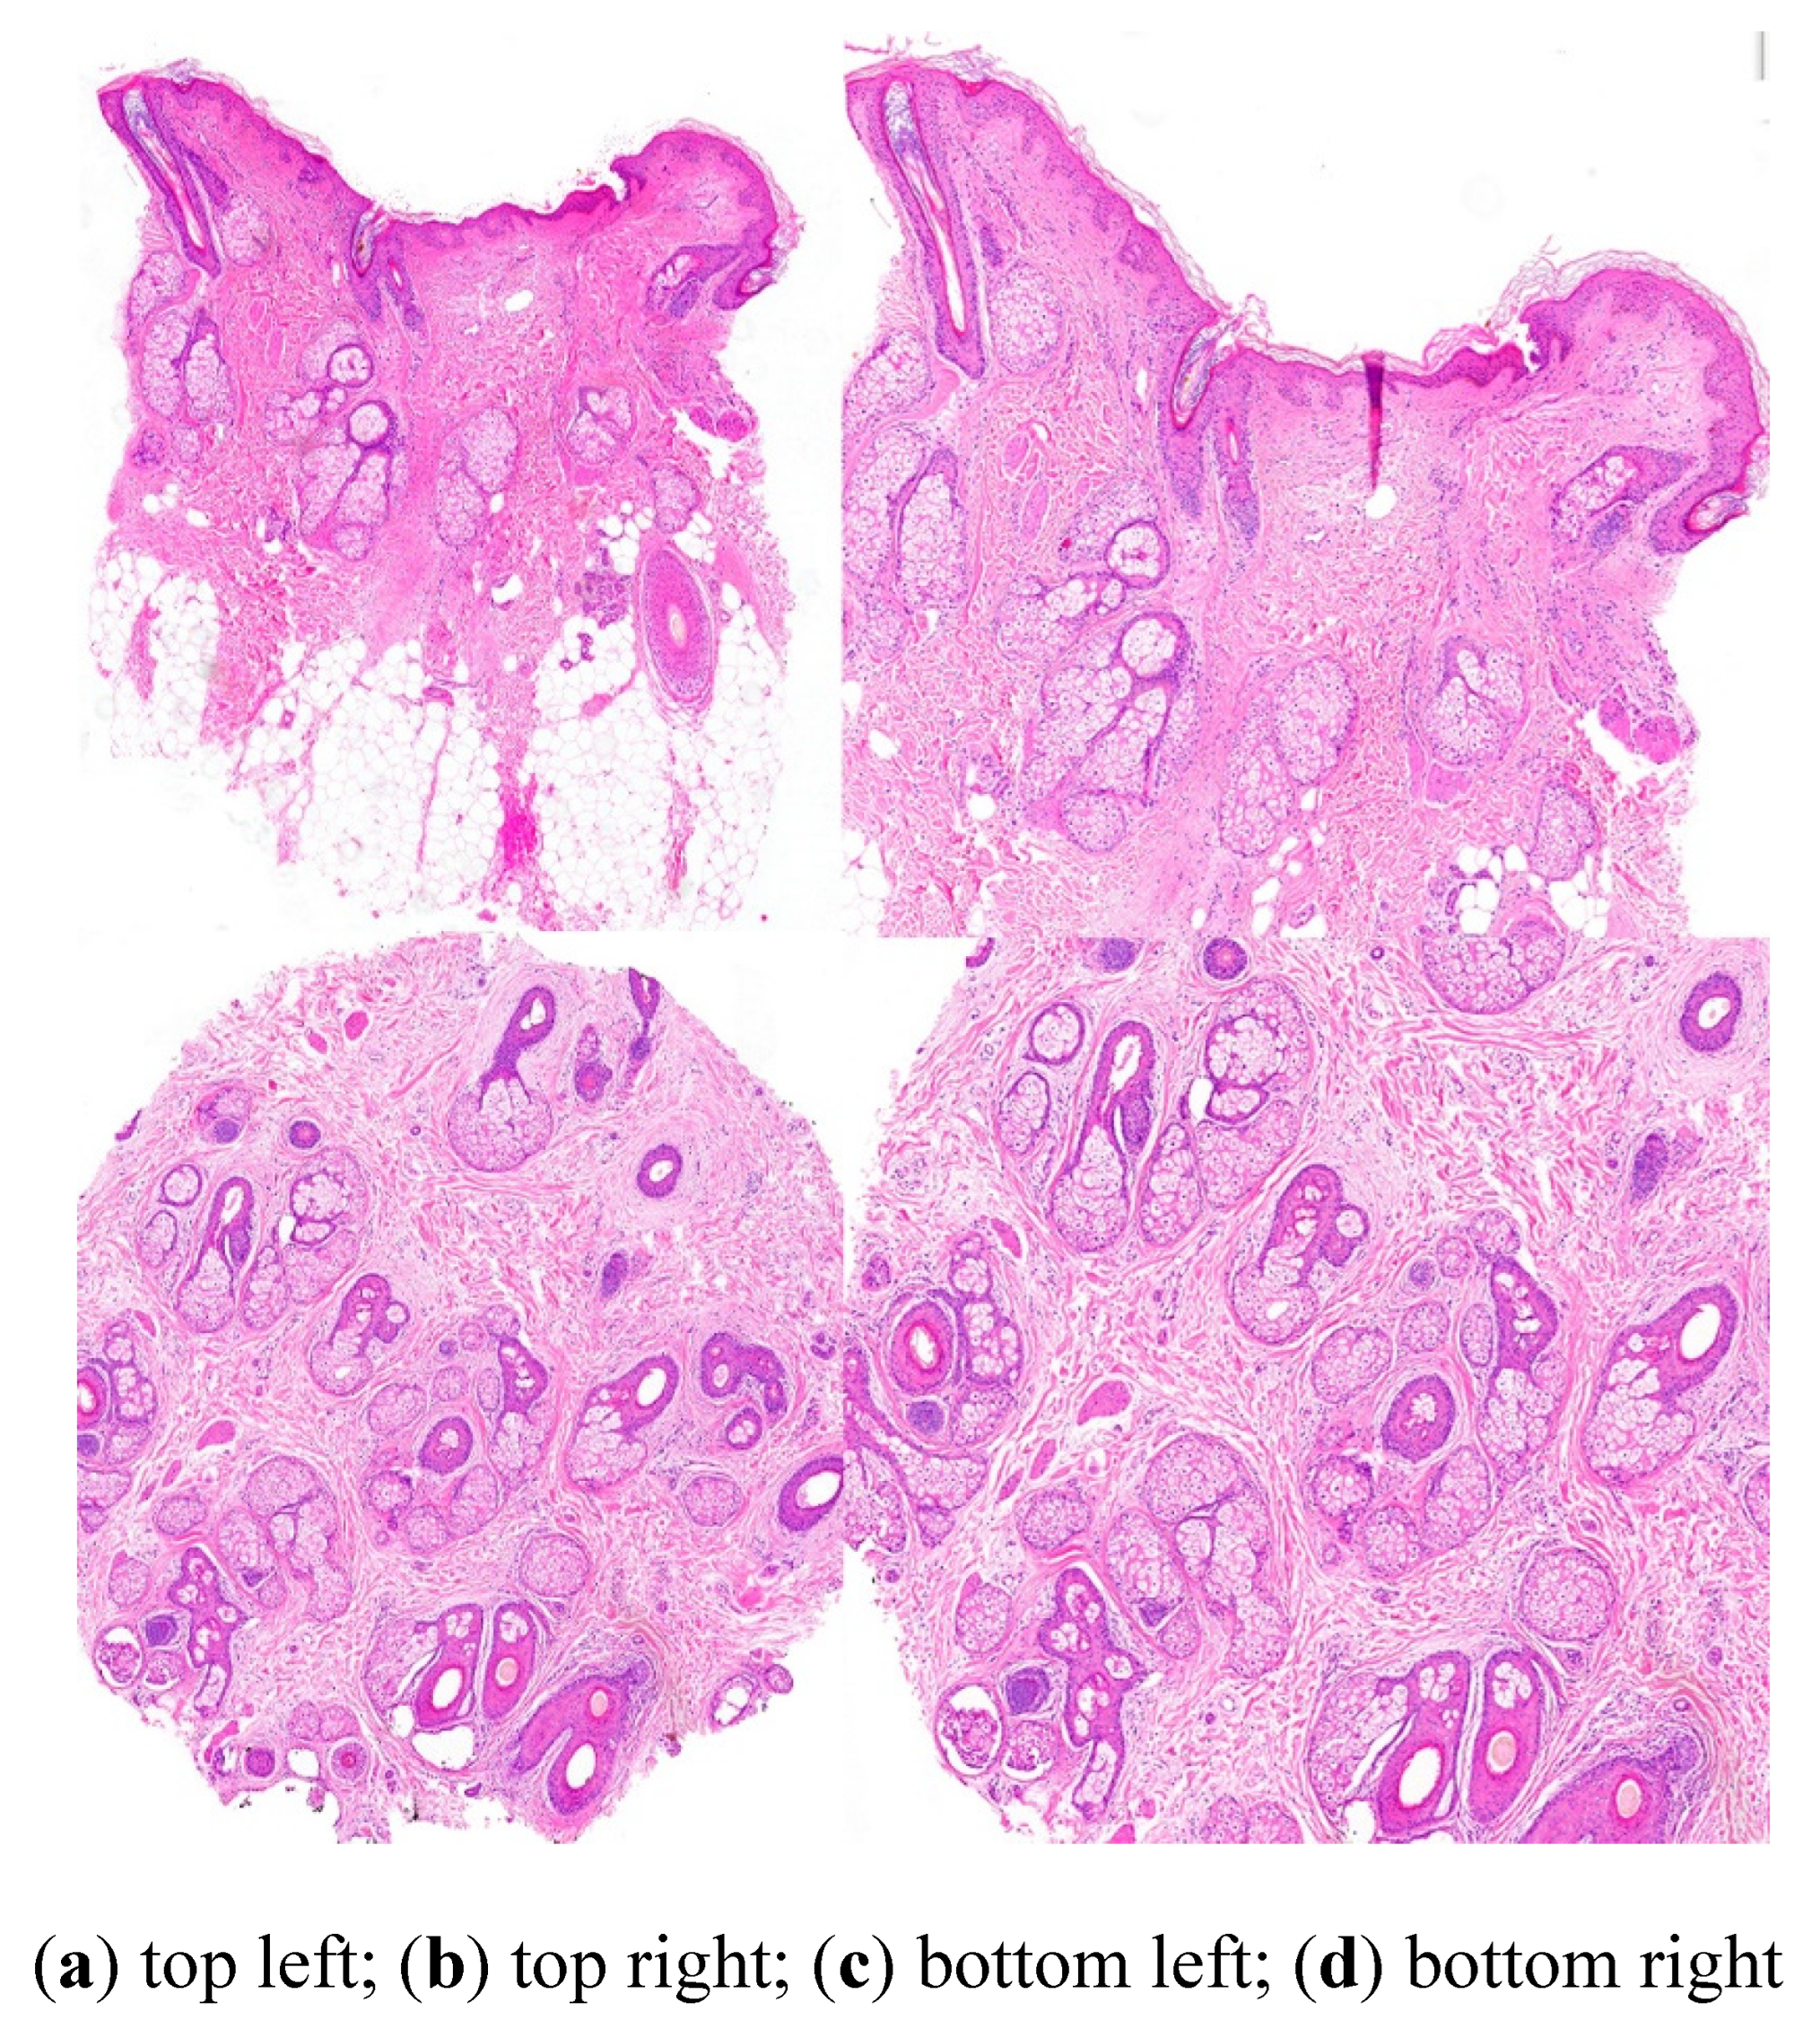

4. Adequate Hair Biopsy